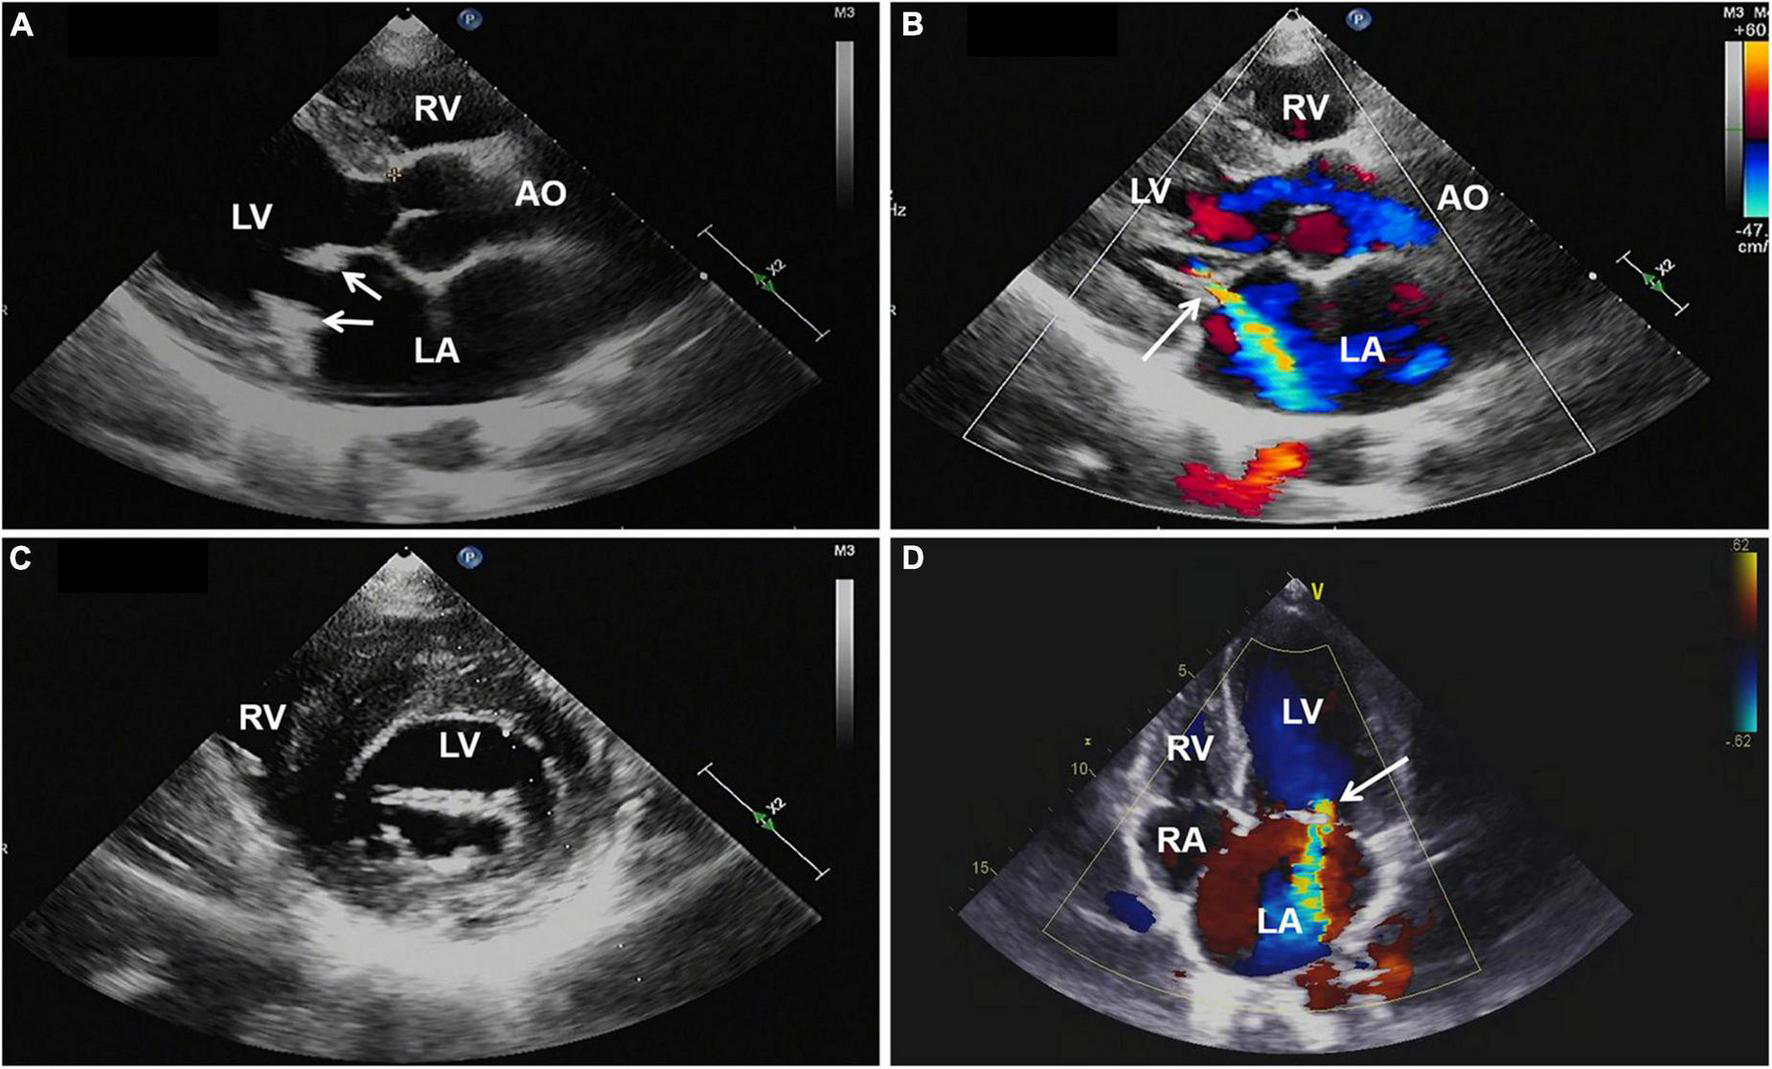

Magnetic resonance imaging (MRI) of the brain was then performed, showing multiple infarctions and softening lesions in the right thalamus, paraventricular area, and cerebellar hemisphere (Figure 1). Magnetic resonance arteriography (MRA) showed right middle cerebral artery occlusion. A carotid ultrasound scan was normal. Transthoracic echocardiogram (TTE) demonstrated that the cusps of the anterior and posterior mitral valve leaflets were thickened. Additionally, verrucous and nodular vegetations with heterogeneous echo-density could be seen at the commissural border of both mitral valve leaflets (Figures 2A,C). The vegetations were firmly attached to the surface of the valve without obvious independent motion. Mild to moderate mitral regurgitation was detected at the central commissure when the valve closed (Figures 2B,D) with an effective regurgitant orifice area (EROA) of 0.25 cm2 and the regurgitant volume of 36 mL. The other valves were morphologically normal. The left ventricular function was normal, with a left ventricular ejection fraction (LVEF) of 60%. Repeated blood cultures were negative, and the patient had no recent history of fever. Considering these findings, the patient was diagnosed with primary APS, LSE, and cerebral infarction. Symptomatic treatment was provided to her during hospital admission with sufficient low molecular weight heparin and warfarin anticoagulation. Oral prednisolone acetate (15 mg/day) and warfarin were administered after her discharge.

FIGURE 2

(A,C) Transthoracic echocardiography showing thickened mitral valve leaflets with verrucous, nodular, heterogeneous echoic vegetations located on the commissural border of both leaflet tips (arrows). (B,D) Color Doppler imaging revealing mild to moderate mitral regurgitation (arrow). AO, aorta; LA, left atrium; LV, left ventricle; RA, right atrium; RV, right ventricle; TTE, transthoracic echocardiography.